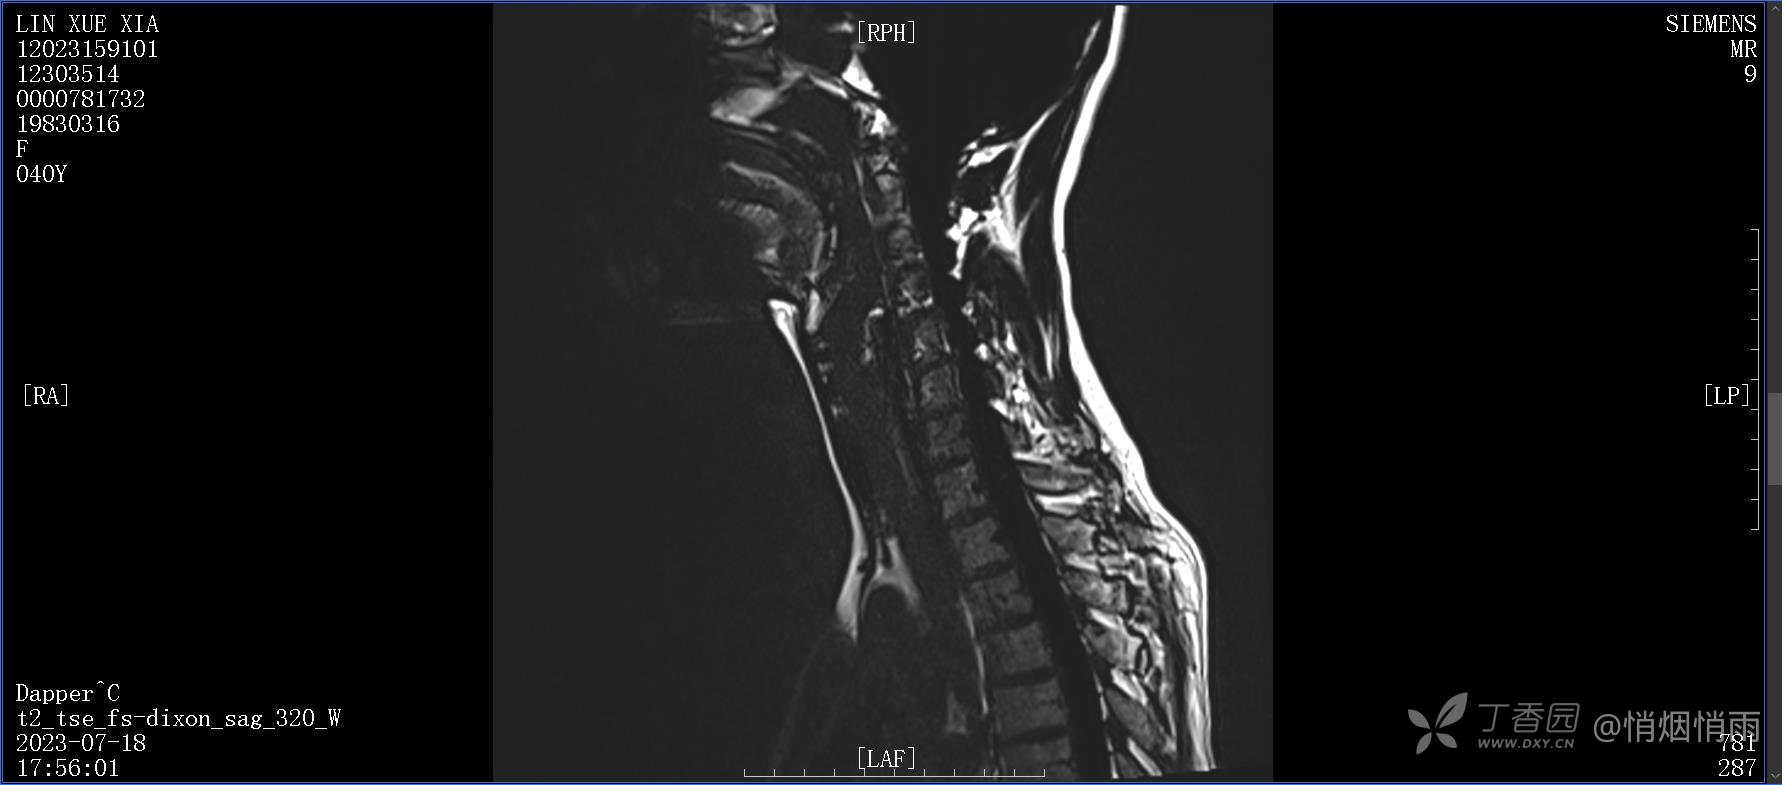

NeurothinkerZ 推荐患者女性,40岁,因右肩背部疼痛班活动受限4日余入院(2023-07-17)。

病史:入院前4天无明显诱因突然感右肩背疼痛伴随活动受限,自行口服依托考昔、艾瑞昔布等药物治疗,院外应用肩关节局部手法按摩等,均无明显改善。外院门诊诊为颈椎病。自诉既往多次“胸椎小关节紊乱”于当地诊所行手法按摩,治疗后好转,否认慢性疾病病史、外伤史、手术史,诉青霉素过敏,无其他药物食物过敏史,否认吸烟史、饮酒史,月经正常,经量正常。

查体:右肩关节局部轻度肿胀,肩胛区压痛明显,痛处不固定,肩关节痛性活动受限,jobe test(+),lift -off test(+),中指、环指感觉较余指减退,余肢端感觉及血运情况可。

目前的诊断,暂时依据辅助检查诊为肩袖损伤,但是患者疼痛的性质和特点,却不是单纯的肩袖损伤所致。考虑过胸廓出口综合征,但是该疾病会出现肩胛区的疼痛吗?(由于考虑到费用的问题,没再进行下一步的检查)带状疱疹会有如此的症状吗?